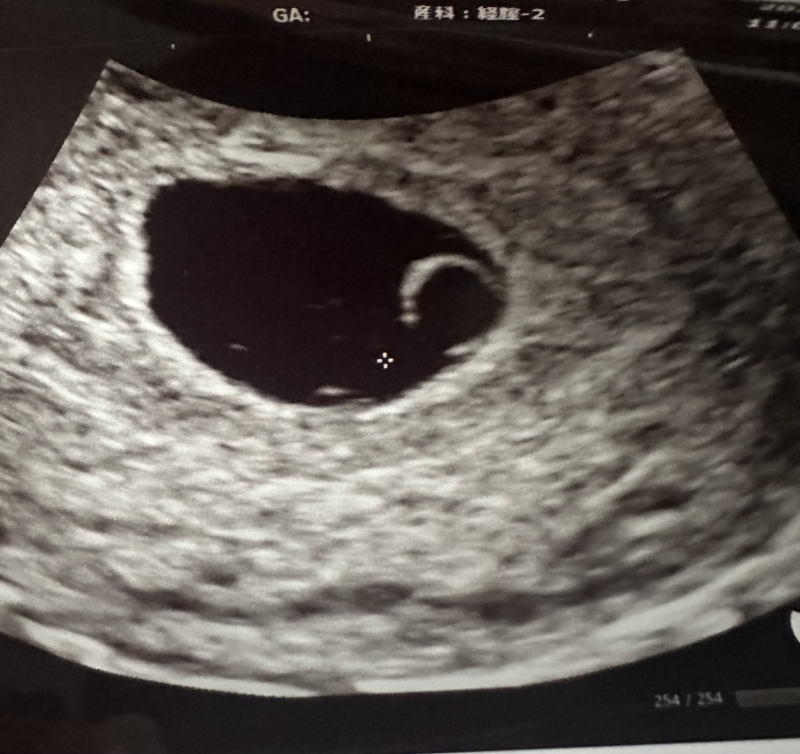

黒っぽい茶色の出血にぼろぼろカスみたいなのが

1週間程続いており量も少しずつ段々と増えてきていて痛みはないのですが、昨日検診で先生に伝えると6週目頃(15mm)と大きさも変わっていない心拍確認できず稽留流産の可能性があると言われました。

(エコー写真7週目)(2枚目はトイレに付いていた茶色いカスみたいなものです)